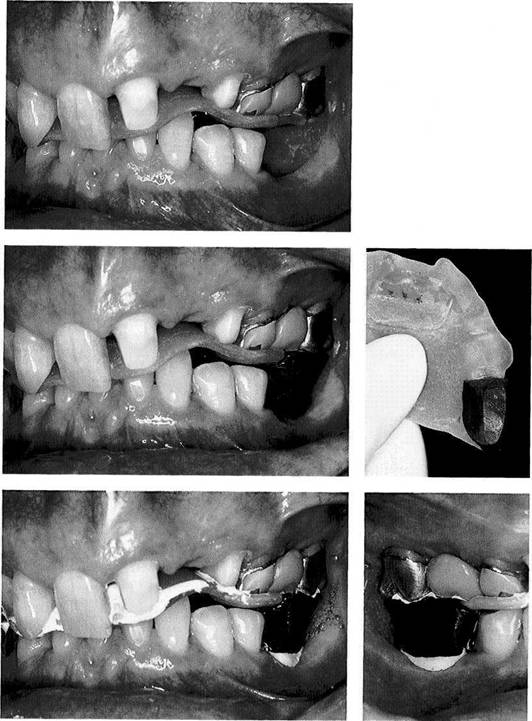

Occlusal pretreatment

Left: The pretreatment on this pa­tient has been completed with the help of a canine-guided equilibra­tion splint. The patient is free of her previous complaints, and maximal intercuspation with the splint has been stable for 4 weeks.

Right: The occlusal contacts have been marked on the splint with black articulating film.

Application of registration paste

Left: Testing the eccentric occlu­sion. The excursive paths marked with red articulating film extend equally. No excursive interferences can be detected in the posterior re­gions.

Right: A fine-detail registration paste is applied to the splint only over the first premolars and distal-most mo­lars.

Registration of the maximum intercuspation position on the splint

Left: With the head in the upright position, the patient closed gently against the splint. After the regis­tration paste has hardened, the previously marked centric contacts should always be visible at the depths of the occlusal imprints.

Right: In preparation for mounting the mandibular cast, the "splint registration" is seated on a dupli­cate maxillary cast made before the splint was constructed.

Pattern of occlusal contacts

Left: The pattern of occlusal con­tacts in maximum occlusion as seen on the splint at the conclusion of splint therapy.

Right: Following removal of the old anterior crowns and additional tooth preparation, the splint is readapted to the incisor prepara­tions, here with impression com­pound and Temp Bond cement.

572 Adapting the splint base to the crown preparations

Left: After removal of the crowns from the distal-most molars, the splint is further adapted on both sides. The original position of the splint relative to the maxilla re­mains unaltered throughout.

Right: Preliminary preparation of the mandibular incisors and ca­nines.

Successive adaptation of the splint occlusion

Left: As soon as the lower canines are prepared for crowns and the distal-most lower crowns are re­moved, the contact of the occlusal device with these preparations is re-established step by step. This preserves the jaw relation estab­lished with the treatment splint.

Right: Mounting of the working casts, here for fabrication of long-term provisional crowns, com­pletes transfer of the stable splint intercuspation position from the patient to the articulator.